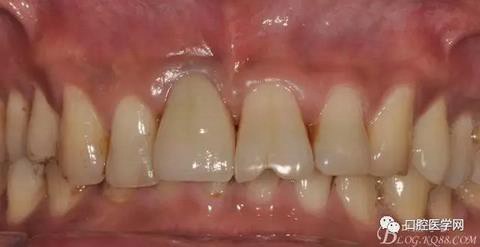

圖4 術(shù)前正位頜面照